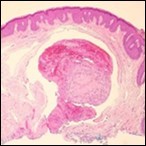

On microscopy, superficial squamous epithelial surface is intact. Sub-epithelial connective tissue stroma exhibits slit-like, vascular spaces. Upon extended magnification, multiple, intravascular papillary projections encompassed within a hyalinised stroma are discerned. Centroidal calcification appears in combination with intravascular, papillary endothelial cell proliferation, lined with singular layer of endothelial cells devoid of cytological atypia6, 7.

Characteristically, the vascular neoplasm denominates numerous papillae within blood vessels. Papillae are coated with singular or dual layer of flattened endothelial cells with an encompassing hyalinised, fibrous tissue core. Vascular lumen is distended with thrombosis. Foci of haemorrhage with fibrinous and purulent exudate are discerned. Tumour perimeter depicts inflammatory granulation tissue. Cholesterol clefts and focal reactive bone formation may concur. Extraneous squamous epithelium may be discontinuous and ulcerated. The neoplasm is devoid of features of malignancy4, 6.

Numerous micro-calcifications can be observed within the lesion which may engender vascular occlusion and tissue necrosis6. Figure 1, Figure 2, Figure 3, Figure 4, Figure 5, Figure 6, Figure 7, Figure 8.

Figure 3.Papillary endothelial hyperplasia exemplifying papillary configuration with endothelial cell layering and a superimposed stratified squamous epithelial lining 12.